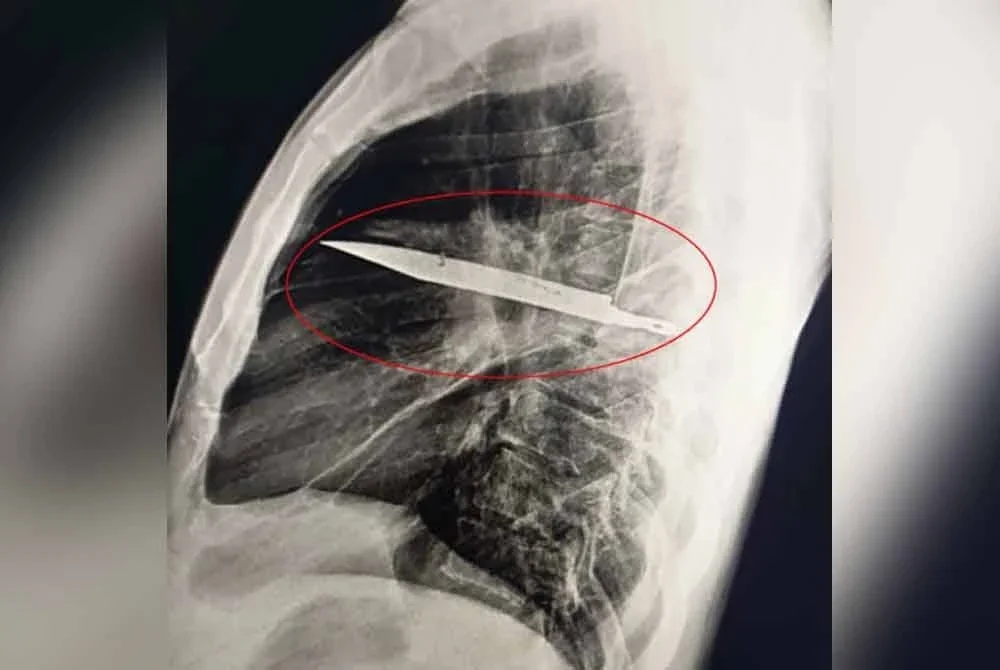

Pemeriksaan sinar X yang dilakukan ke atasnya membuat penemuan mengejutkan iaitu sebilah pisau tertanam pada dadanya yang didakwa berpunca daripada insiden pergaduhan kira-kira lapan tahun lalu.

"Dia bernasib baik kerana objek tajam itu tidak mengenai mana-mana organ utama. Doktor yang merawatnya sebelum ini mungkin tidak menjalankan pemeriksaan radiologi susulan selepas dia tidak mengadu sakit selepas lukanya sembuh," menurut laporan kajian tersebut lagi.

Difahamkan, pisau yang tertanam itu menyebabkan ketidakselesaan kepadanya untuk tempoh yang lama dan cairan nanah itu terhasil daripada tisu mati yang terkumpul di sekeliling objek asing. - Agensi